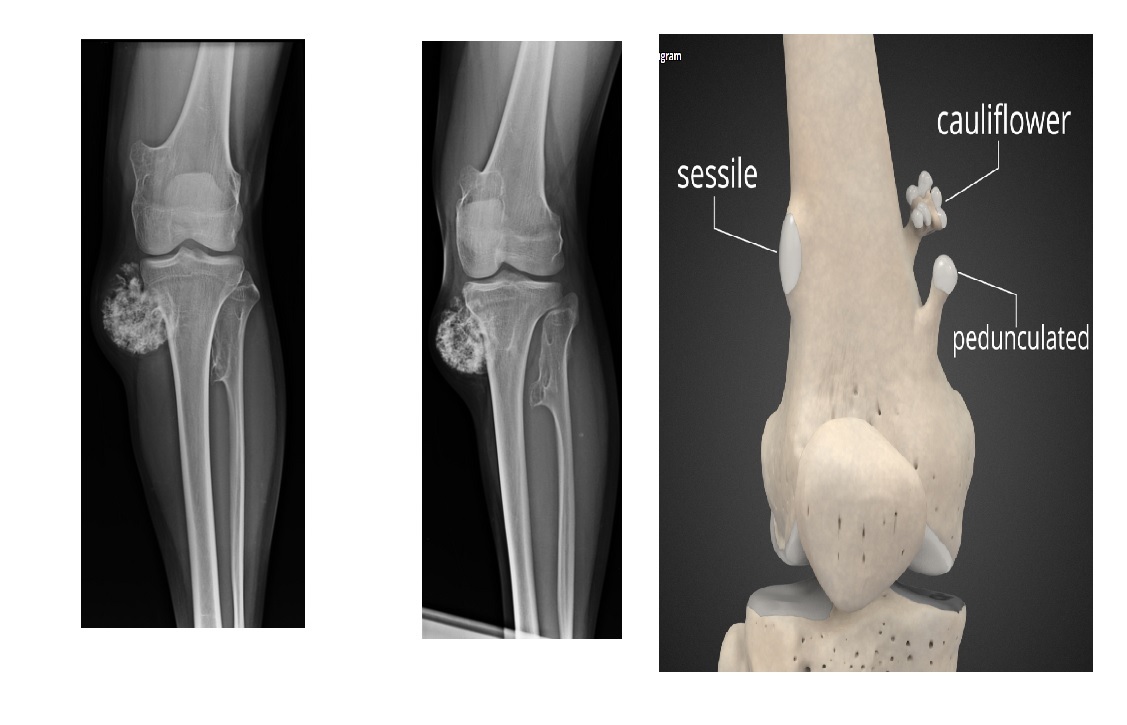

Osteochondroma

points away from the joint

Pedunculated lesion arising from surface of bone with continuity of normal cortex and marrow

Metaphysis/metaphyseal equivalents (rarely diaphysis)

Multiple =

Diaphyseal aclasia/Multiple Hereditary Exostoses - Metaphysis region of tubular bones of extremities

Cap > 1.5cm ??? chondrosarcomatous transformation

ng. avian spur points towards the joint